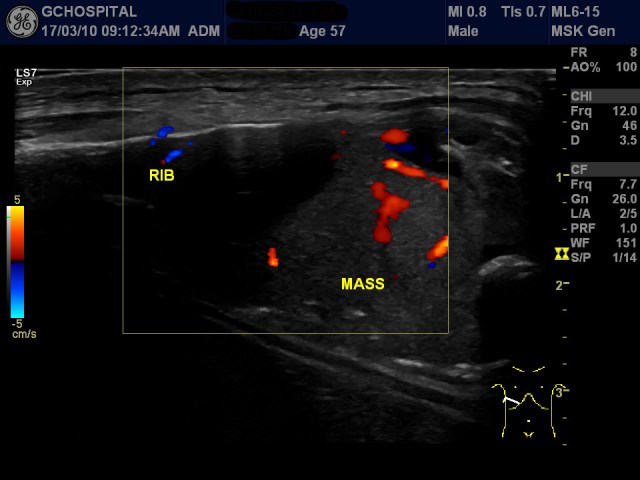

57세 남자환자로, 수술이 불가능할정도로 퍼진 간암이 진단되어 요양 중 우측 흉벽에 통증을 동반한 종괴가 만져져 내원하셨습니다. 초음파영상에서 우측 8번 늑골의 끝부분에 풍선처럼 부풀어오른 종괴가 보였고, 근초 갈비뼈의 피골을 파괴시키는 양상이었습니다.

도플러영상에서 종괴는 혈관이 매우 풍부했지만, 내부에 괴사나 석회화같은 이차적인 변회소견은 없었습니다.